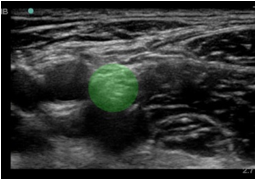

Bild: Markierung des Nervus femoralis

Markierter Bereich: Femorale Nervenblockade